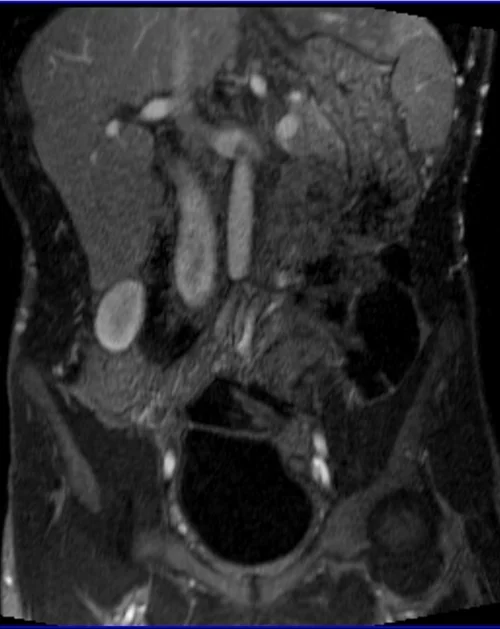

MRA Renal Arteries